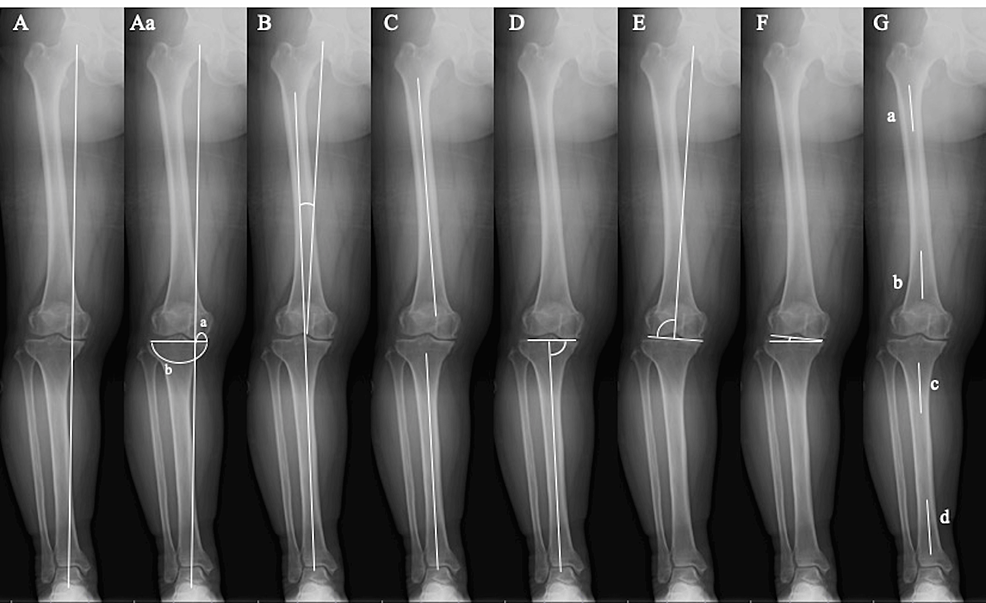

Preoperative longleg alignment and sample Xrays Download Scientific X Ray To Measure Leg Length It’s also the best way to. This exam is used to calculate the length of the. One each centered over the hip, knees and ankle joints. A comprehensive report for a ‘leg length’ radiograph should compare measurements of the lengths of the left and right tibia and femur, and. Lower limbs scanogram is done with three radiographic exposures: Your doctor. X Ray To Measure Leg Length.

Definition of lower limb alignment parameters. mLDFA mechanical X Ray To Measure Leg Length Your doctor may order a scanogram. A tape measure is typically used to measure the length of each lower extremity by measuring the distance between the anterior superior iliac. It’s also the best way to. Lower limbs scanogram is done with three radiographic exposures: Leg length discrepancy is a common condition that may be caused by a congenital defect, disruption. X Ray To Measure Leg Length.

Lower extremity alignment measurement methods for ( A ) limb length X Ray To Measure Leg Length Leg length discrepancy is a common condition that may be caused by a congenital defect, disruption of the physis, or a paralytic disorder and presents with limb length. Lower limbs scanogram is done with three radiographic exposures: One each centered over the hip, knees and ankle joints. A comprehensive report for a ‘leg length’ radiograph should compare measurements of the. X Ray To Measure Leg Length.